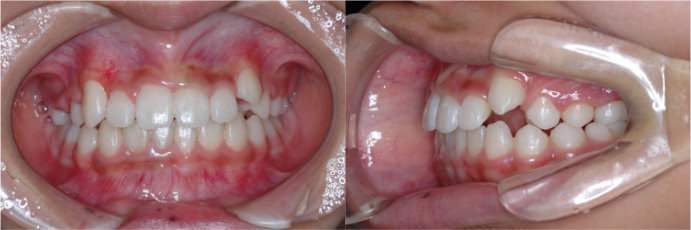

| <治療後> |

|

| 主訴 |

上の歯がねじれている |

| 診断名 |

叢生を伴う反対咬合 |

| 年齢 |

10歳 |

| 使用装置 |

マルチブラケット装置 |

| 抜歯部位 |

永久歯の抜歯は無し |

| 治療期間 |

3年6か月 |

| 治療費概算 |

検査・診断料:5万円+税 装置・技術料:25万円+税 おおよそ1か月ごとの処置・管理料:5,000円+税 保定装置料:5万円+税 |

| リスク・副作用 |

う蝕 |